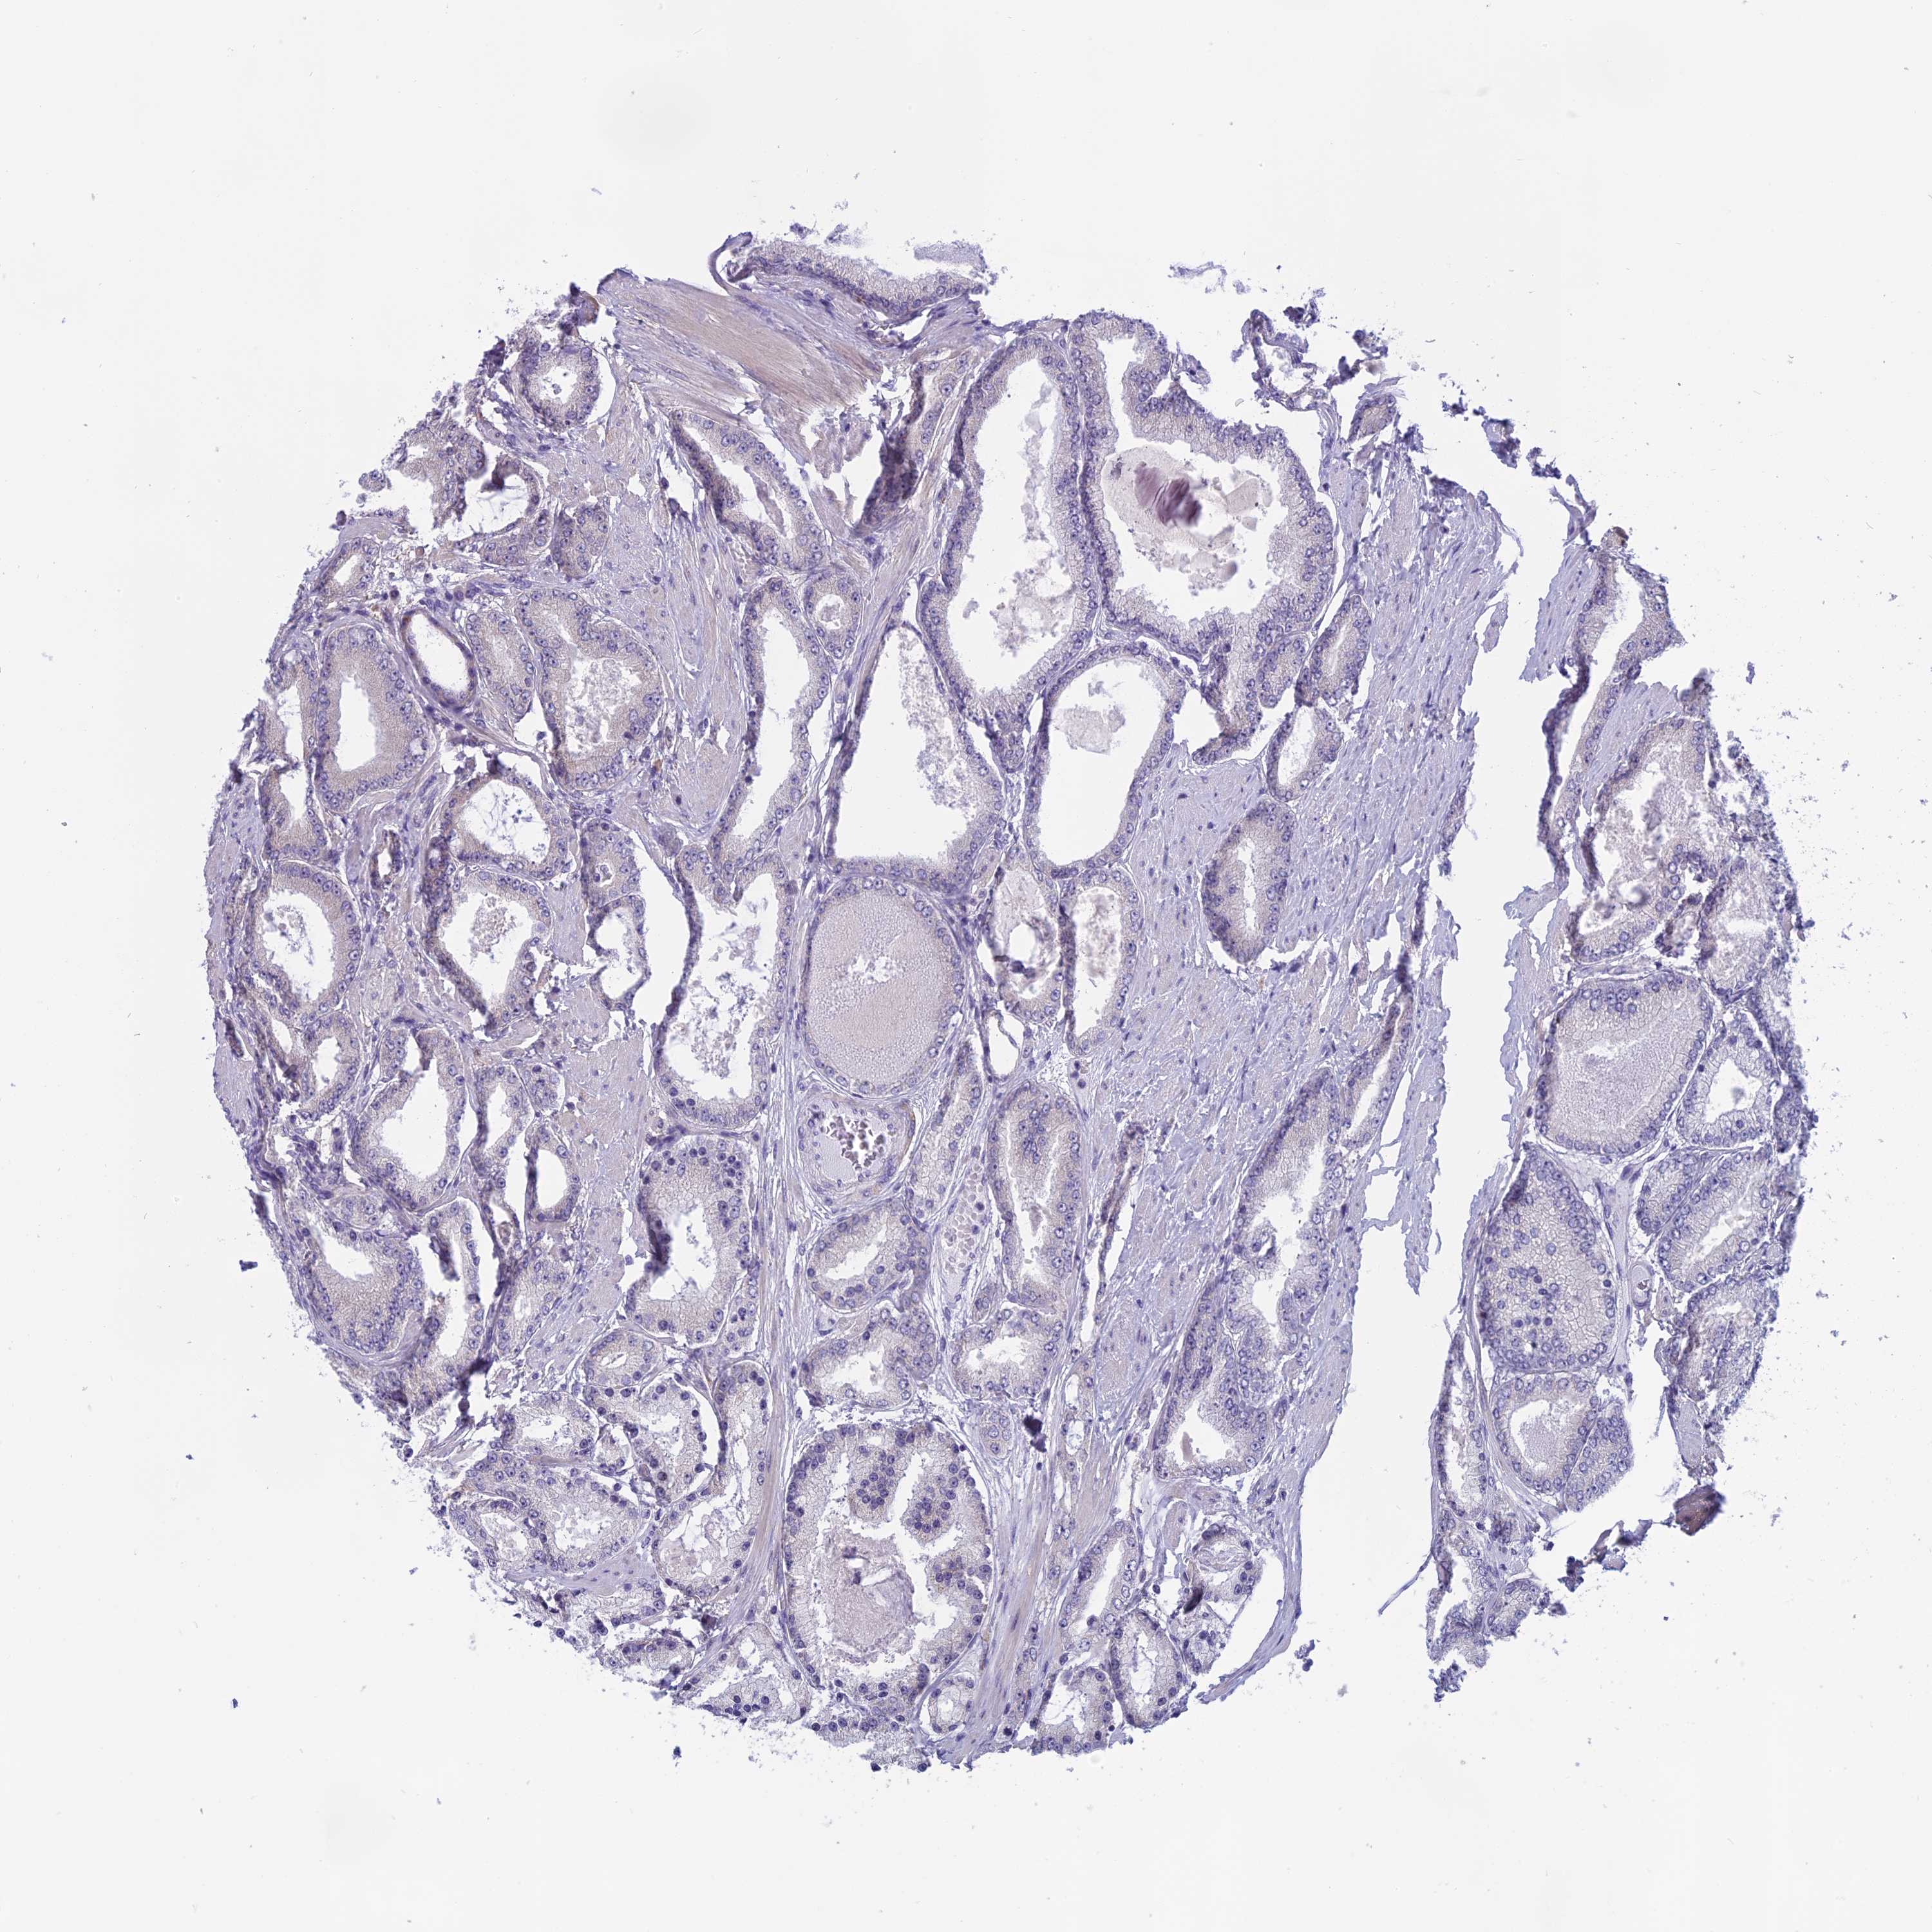

PROSTATE CANCER - Protein expressioni

A mouse-over function shows sample information and annotation data. Click on an image to view it in a full screen mode. Samples can be filtered based on level of antibody staining by selecting one or several of the following categories: high, medium, low and not detected. The assay and annotation is described here.

Note that samples used for immunohistochemistry by the Human Protein Atlas do not correspond to samples in the TCGA dataset.

Antibody stainingi

Antibody staining in the annotated cell types in the current human tissue is reported as not detected, low, medium, or high, based on conventional immunohistochemistry profiling in selected tissues. This score is based on the combination of the staining intensity and fraction of stained cells.

Each image is clickable and will lead to virtual microscopy that enables deeper exploration of all samples and also displays staining intensity scores, fraction scores and subcellular localization as well as patient and tissue information for each sample.

Antibody HPA043885

Antibody HPA053487

Staining

High

Medium

Low

Not detected

Intensity

Strong

Moderate

Weak

Negative

Quantity

>75%

75%-25%

<25%

None

Location

Nuclear

Cytoplasmic/membranous

Cytoplasmic/membranous,nuclear

Adenocarcinoma, NOS

Adenocarcinoma, High grade

Adenocarcinoma, Low grade